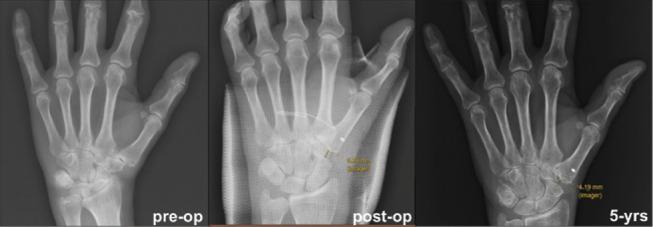

85 consecutive modified Ceruso's suspensionplasty were performed from 2012 and 2018. All the patients were evaluated at an average 5.1-year follow-up (21-96 months). Subjective patient satisfaction rate, NRS, DASH score, abduction angle, Kapandji score and pinch strength using functional tests were assessed. The scapho-metacarpal distance was measured at follow-up radiographs.

90.6% of the patients were satisfied by the treatment. The NRS and the DASH score improved (from 8.5 pre-operatively to 1.53 and from 87.5 to 24.6 respectively-p<0.001). The Kapandji test was rated from 7 to 10 in 65.9% of the patients. The pinch strength was good in 75.3% of the patients at follow-up. The abduction angle of the thumb was 38.2° (20°-55°). The mean scapho-trapezial distance decreased of 2.45 mm (from 9.87 mm to 7.42 mm - p<0.05). 8 patients had persistent pain and thumb disfunction, 1 patient had De Quervain's tenosynovitis.